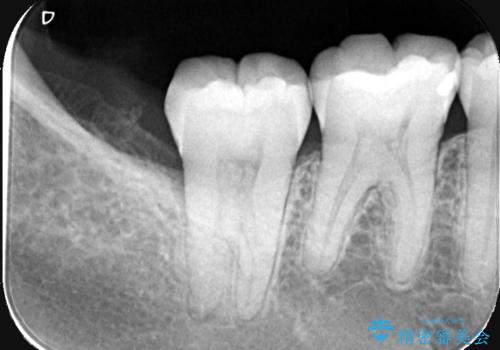

来院時、右下7遠心9mm、舌側6mmと深い歯周ポケットを認めました。

遠心から舌側、唇側に及ぶ深い垂直的骨欠損も認めたため、歯科衛生士による歯周基本治療の後、歯周外科(再生療法)を行いました。

レントゲン写真は、処置後一年経過時のもので、歯周ポケットは遠心4mm、舌側3mmまで減少、出血なし。

一度目の再生療法でできる骨形態は移行的でないこともあるため、経過を診つつ骨整形も必要であれば今後行う予定です。